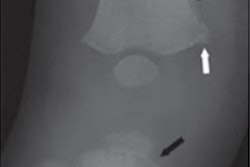

The document covers training requirements for imaging staff and the specific radiographs and time frames needed for initial and follow-up skeletal surveys. The authors recommend more skeletal views, both for the initial exams and for follow-up. New advice is given on sedation and the use of CT for the detection of rib fractures.

Optimal neurological imaging and time frames are covered, as well as postmortem imaging. For neurological exams, they recommend that MRI of the spine is included, along with cranial MRI, because there is new evidence in this area.